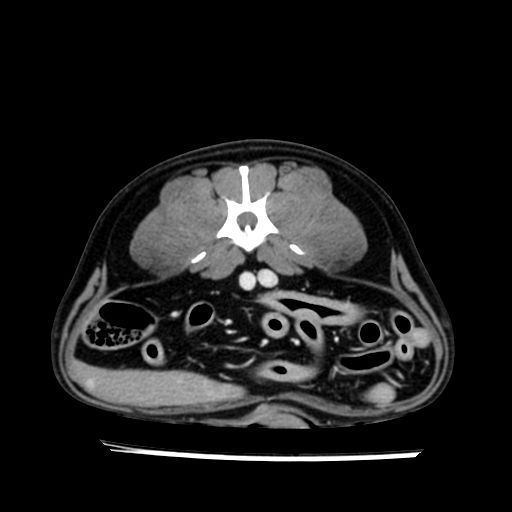

prescritto esame TAC

sequenza immagini limitata al fegato reni e surreni

le immagini ecografiche rispetto alla tac datano circa 7 mesi prima ,le surrenali sono normali nonostante il test acth sia risultato positivo .all’esame TAC dopo diversi mesi risultano aumentate armonicamente nel volume e si individua un forte sospetto di adenoma ipofisario .

sospetto adenoma ipofisario vs. meno probabilmente meningioma della base; intertiziopatia polmonare; lesione espansiva epatica, verosimilmente del lobo laterale sinistro, di sospetta natura neoplastica; lesioni spleniche di natura da definire; iperplasia/ipertrofia delle ghiandole surrenali, bilateralmente; vertebra di transizione del rachide toracico; tenosinovite cronica del muscolo bicipite brachiale di destra.